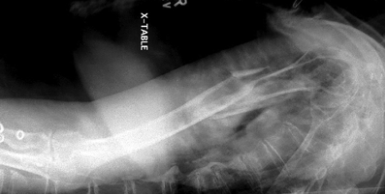

is this a normal or dislocated shoulder? how do you know?

normal, head of humerus superimposed over base of Y

is this a normal or dislocated shoulder? in which direction is it dislocated?

dislocated, anterior